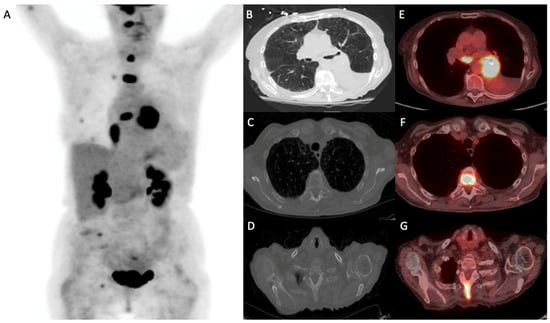

- Liu, J.; Dong, M.; Sun, X.; Li, W.; Xing, L.; Yu, J. Prognostic Value of 18F-FDG PET/CT in Surgical Non-Small Cell Lung Cancer: A Meta-Analysis. PLoS ONE 2016, 11, e0146195. [Google Scholar] [CrossRef]

- Paesmans, M.; Berghmans, T.; Dusart, M.; Garcia, C.; Hossein-Foucher, C.; Lafitte, J.J.; Mascaux, C.; Meert, A.P.; Roelandts, M.; Scherpereel, A.; et al. Primary tumor standardized uptake value measured on fluorodeoxyglucose positron emission tomography is of prognostic value for survival in non-small cell lung cancer: Update of a systematic review and meta-analysis by the European Lung Cancer Working Party for the International Association for the Study of Lung Cancer Staging Project. J. Thorac. Oncol. 2010, 5, 612–619. [Google Scholar] [CrossRef]

- Im, H.J.; Pak, K.; Cheon, G.J.; Kang, K.W.; Kim, S.J.; Kim, I.J.; Chung, J.K.; Kim, E.E.; Lee, D.S. Prognostic value of volumetric parameters of 18F-FDG PET in non-small-cell lung cancer: A meta-analysis. Eur. J. Nucl. Med. Mol. Imaging 2015, 42, 241–251. [Google Scholar] [CrossRef] [PubMed]

- Szyszko, T.A.; Yip, C.; Szlosarek, P.; Goh, V.; Cook, G.J. The role of new PET tracers for lung cancer. Lung Cancer 2016, 94, 7–14. [Google Scholar] [CrossRef] [PubMed]

- Wang, L.; Tang, G.; Hu, K.; Liu, X.; Zhou, W.; Li, H.; Huang, S.; Han, Y.; Chen, L.; Zhong, J.; et al. Comparison of 68Ga-FAPI and 18F-FDG PET/CT in the Evaluation of Advanced Lung Cancer. Radiology 2022, 303, 191–199. [Google Scholar] [CrossRef] [PubMed]

- Zhou, X.; Wang, S.; Xu, X.; Meng, X.; Zhang, H.; Zhang, A.; Song, Y.; Zhu, H.; Yang, Z.; Li, N. Higher accuracy of [68 Ga]Ga-DOTA-FAPI-04 PET/CT comparing with 2-[18F]FDG PET/CT in clinical staging of NSCLC. Eur. J. Nucl. Med. Mol. Imaging 2022, 49, 2983–2993. [Google Scholar] [CrossRef]